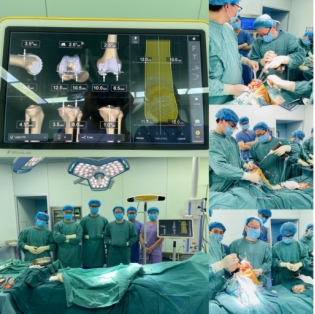

65岁的鲁大爷和69岁的张大爷膝腿疼了好多年,现在路都走不了,得换膝关节,可这么大的手术老人受得了吗?今年年初,重医附二院骨科关节外科中心用计算机导航辅助下人工全膝关节置换(TKA)手术给出了答案:伤口小、恢复快、少遭罪、效果还好!这不,如今每天的晨起遛弯大军中多了两位老人的矫健身影;

计算机导航辅助下人工全膝关节置换(TKA)手术。院方供图